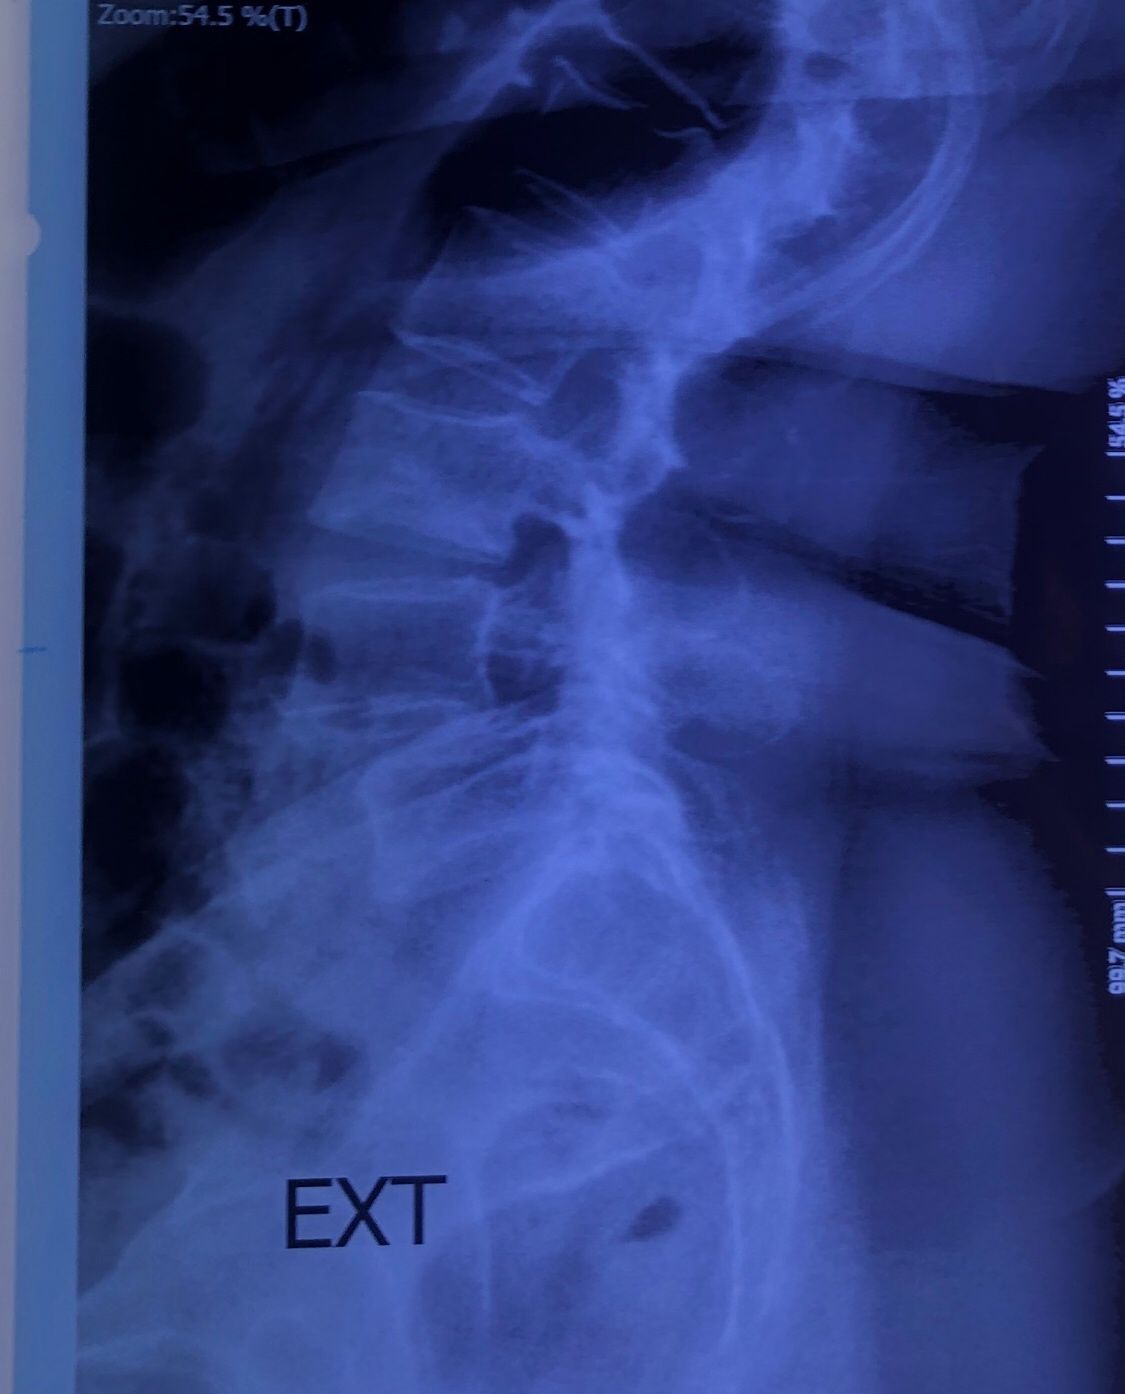

Since I’ve noticed instability in some segments I asked for dynamic L/S x ray:we see mild L4 ant listens due to DjD/DDD. There is not any pars defect.

Is ant listhesis of L4 unstable or stable?